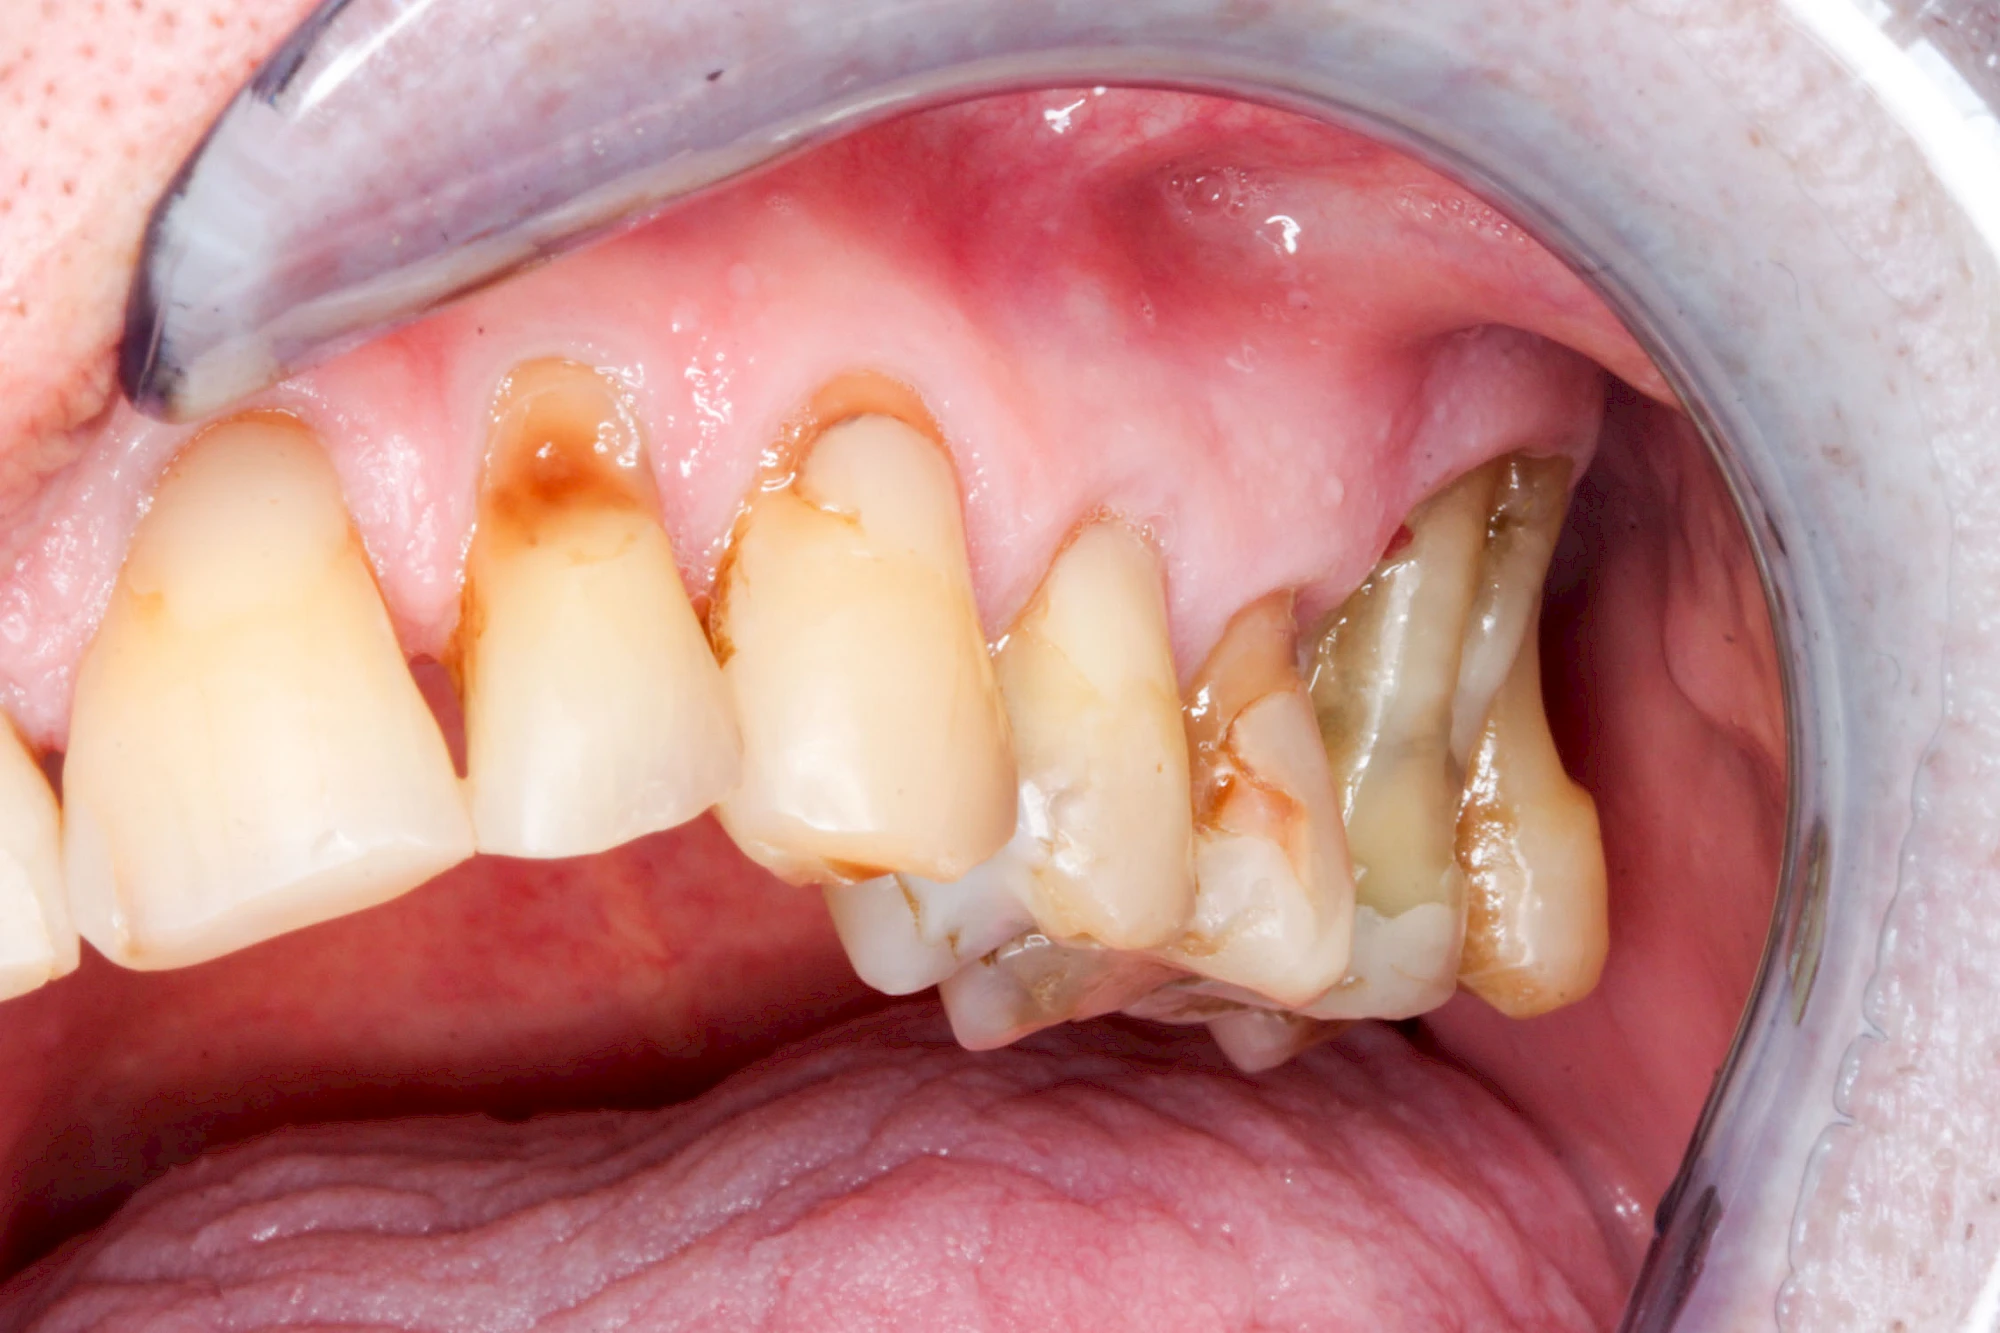

Ist zunächst nur das Zahnfleisch von der Entzündung betroffen, spricht man von Gingivitis. Später, wenn auch der Knochen um die Zähne herum entzündet ist, spricht man von einer Parodontitis. Bei der Parodontitis wird der Knochen nach und nach abgebaut und das Zahnfleisch zieht sich zurück. Die Zahnhälse und Zahnwurzeloberflächen liegen mehr und mehr frei. Die Zähne werden zunehmend lockerer und fallen schließlich aus.

Gingivitis & Parodontitis: Stadien